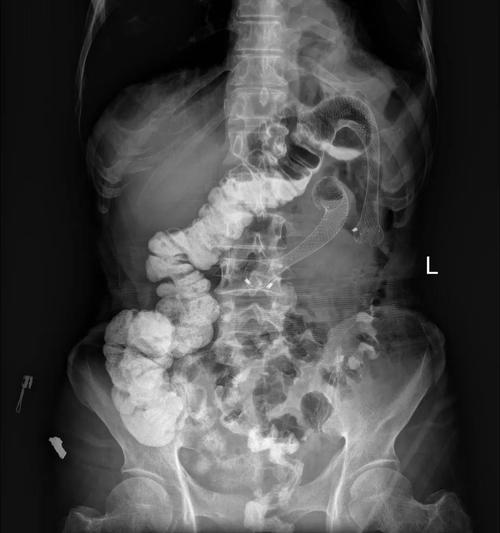

结肠梗阻,大肠梗阻

结 肠 梗 阻 c t 平 扫 ★结肠梗阻—ct平扫见结肠肠腔扩张及结肠

大肠梗阻